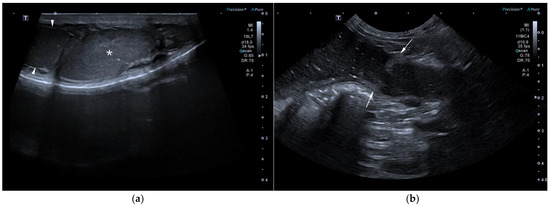

In case 3, the lesion contained an intense neutrophilic, hemorrhagic, and macrophagic luminal infiltrate. The mucosa was extensively ulcerated and necrotic, with distended glands, and a peripheral muscular layer was noted. The wall contained plasma cells, lymphocytes, and neutrophils (Figure 7a). The peritoneal mass consisted of an organized multilobular proliferation divided by broad fibrotic bands, with large peripheral vessels and clusters of vacuolated cuboidal cells. Marked anisocytosis, anisokaryosis, and a high mitotic index were noted (Figure 7b). These features confirmed persistent Müllerian duct remnants with cystic endometrial hyperplasia and ulcerative, suppurative metritis. The mass was consistent with an ovarian granulosa cell tumor. Although no testicular tissue was noted, an ovotesticular origin could not be fully excluded. Cytology of the medial iliac lymph nodes in case 3 revealed abundant round or fragmented nucleated cells, eosinophilic background material, and fine cytoplasmic vacuolization, confirming metastatic lymphadenopathy from the granulosa cell tumor.

Figure 7. Histopathological images of case 3, hematoxylin-eosin staining. (a) 2× magnification. Tubular organ showing an outer circumferential muscular layer (myometrium) and an inner mucosal layer with dilated glands (endometrium). Cellular debris and hemorrhage are present within the lumen; (b) 5× magnification. Granulosa cell tumor composed of neoplastic cells forming irregular cystic cavities with central follicular fluid and peripheral clusters of neoplastic cells, resembling tertiary ovarian follicles.